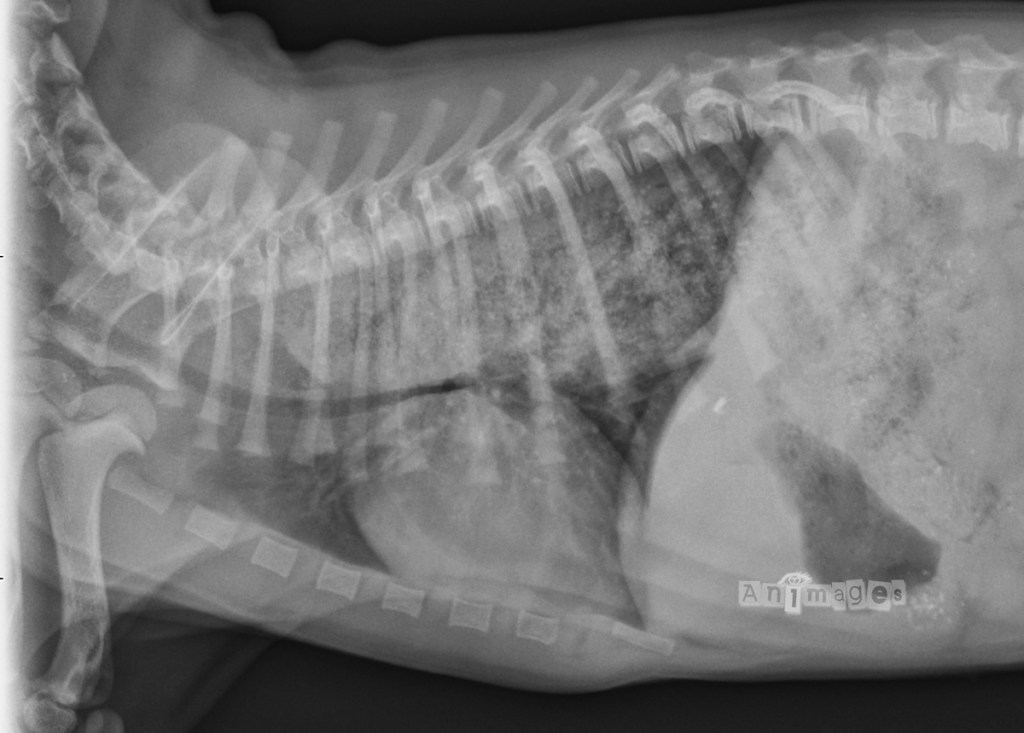

laterale